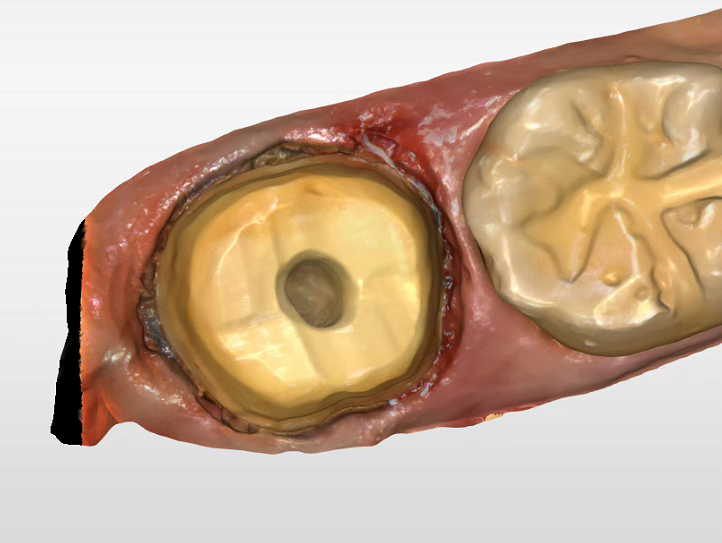

어금니 크라운

Before

After

대량 충치로 손상된 어금니 완전 복원